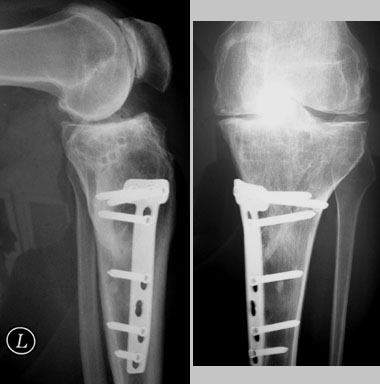

In Zermatt trete ich morgen früh Skitag Nummer 58 dieses Winters an. Gut! Es gibt auch wieder neue Röntgenbilder - auch wenn ich lieber auch links die Qualität des rechten Knies hätte, bin ich ganz zufrieden... kaum Veränderungen.

Röntgenbilder Februar 2009 - Klicken für grössere Fassung